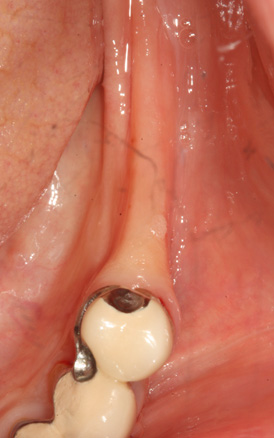

상악동 거상술

상악동 거상술 고난이도 뼈이식술 입니다.

청담네오플란트에서는 상악동 거상술을 비롯한

고난이도 임플란트 시술 노하우가 풍부한 치의학 박사

전문의가 직접 상악동 거상술을 시행합니다

상악동은 윗턱뼈 내부의 구조물로서 개개인에 따라 생김새가 다릅니다.

상악동의 바닥이 잇몸뼈 방향으로 많이 내려온 경우, 임플란트를 식립하기에

잇몸뼈가 부족하게 됩니다. 이러한 경우 상악동 내부로 뼈이식을 하는

상악동 거상술이 필요하게 됩니다.